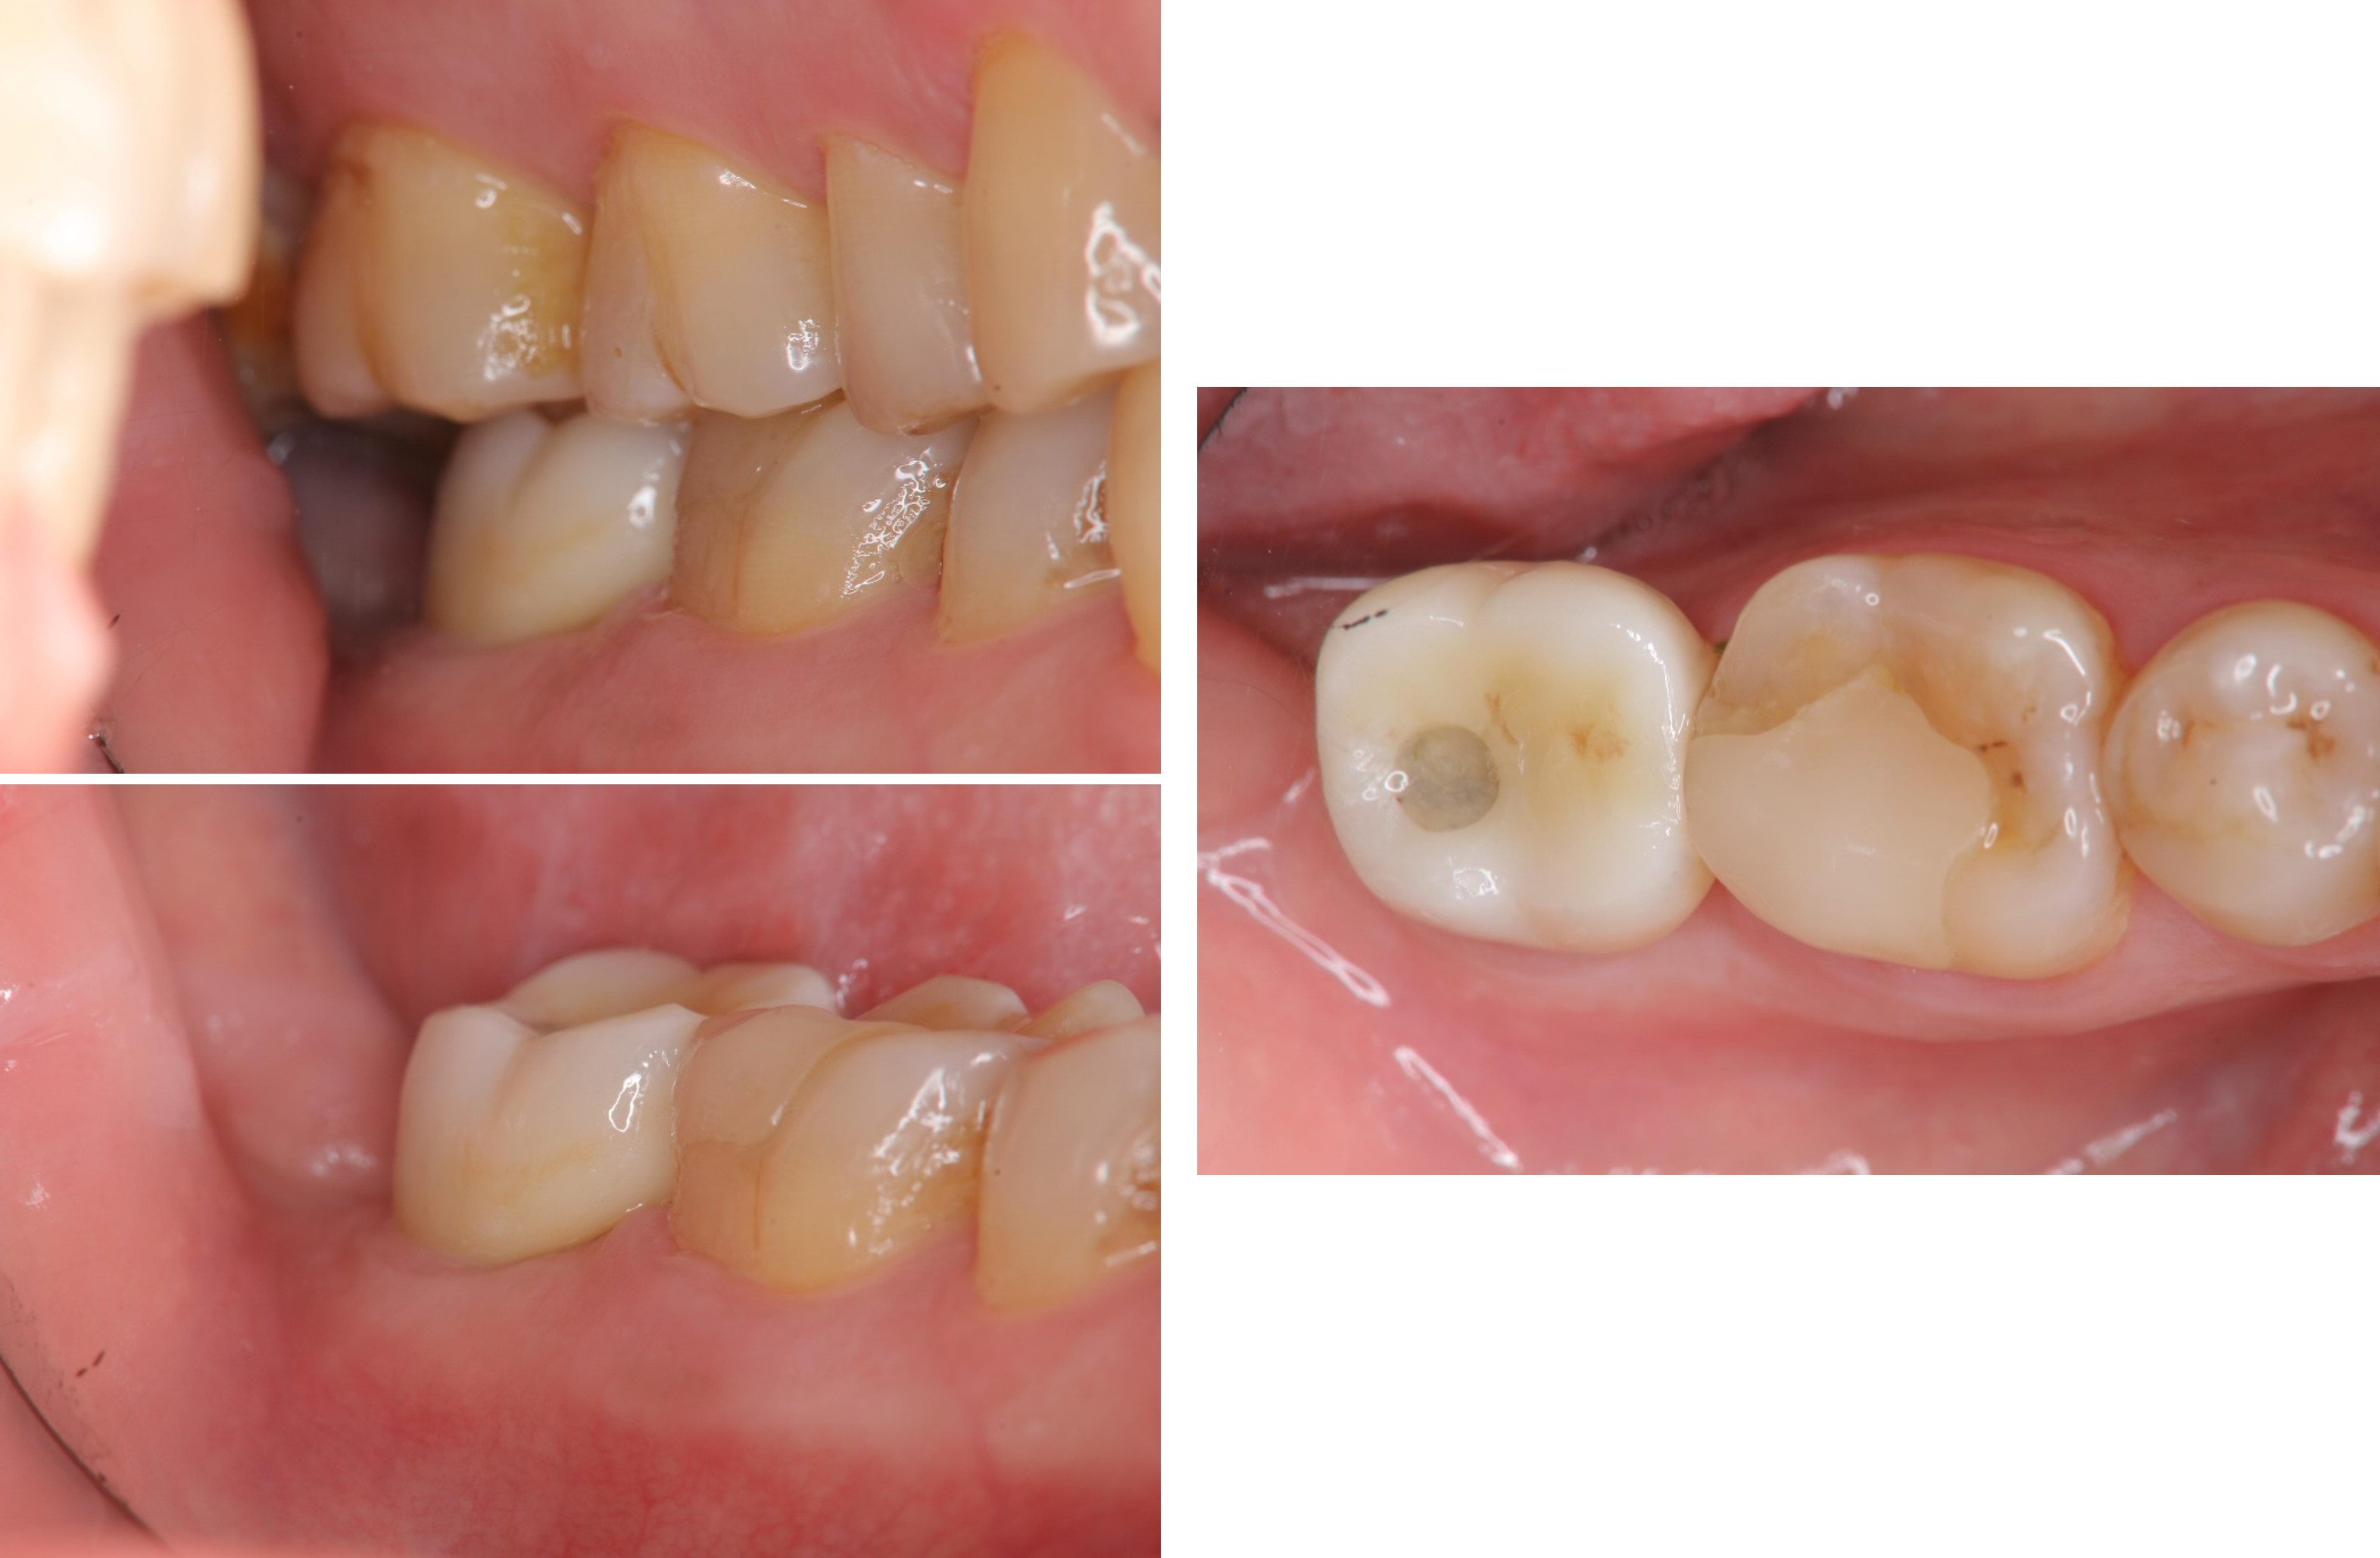

治療前,二次蛀牙,咬頭受損

蛀牙未到牙髓